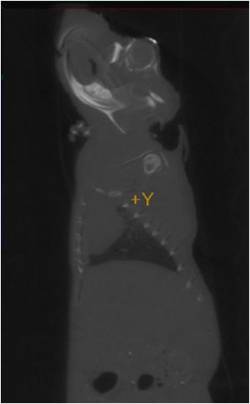

Figure 3. Left and right sagittal CT images of mouse with iodinated liposome injected in left eye vein